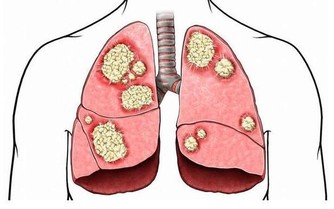

另外,美國賓夕法尼亞州立大學醫院的研究人員在研究中發現,醒來30-60分鐘吸煙的人罹患肺癌的機率是醒來1小時候再抽煙的人的1.31倍,而一覺醒來就抽煙的人則是1.79倍。